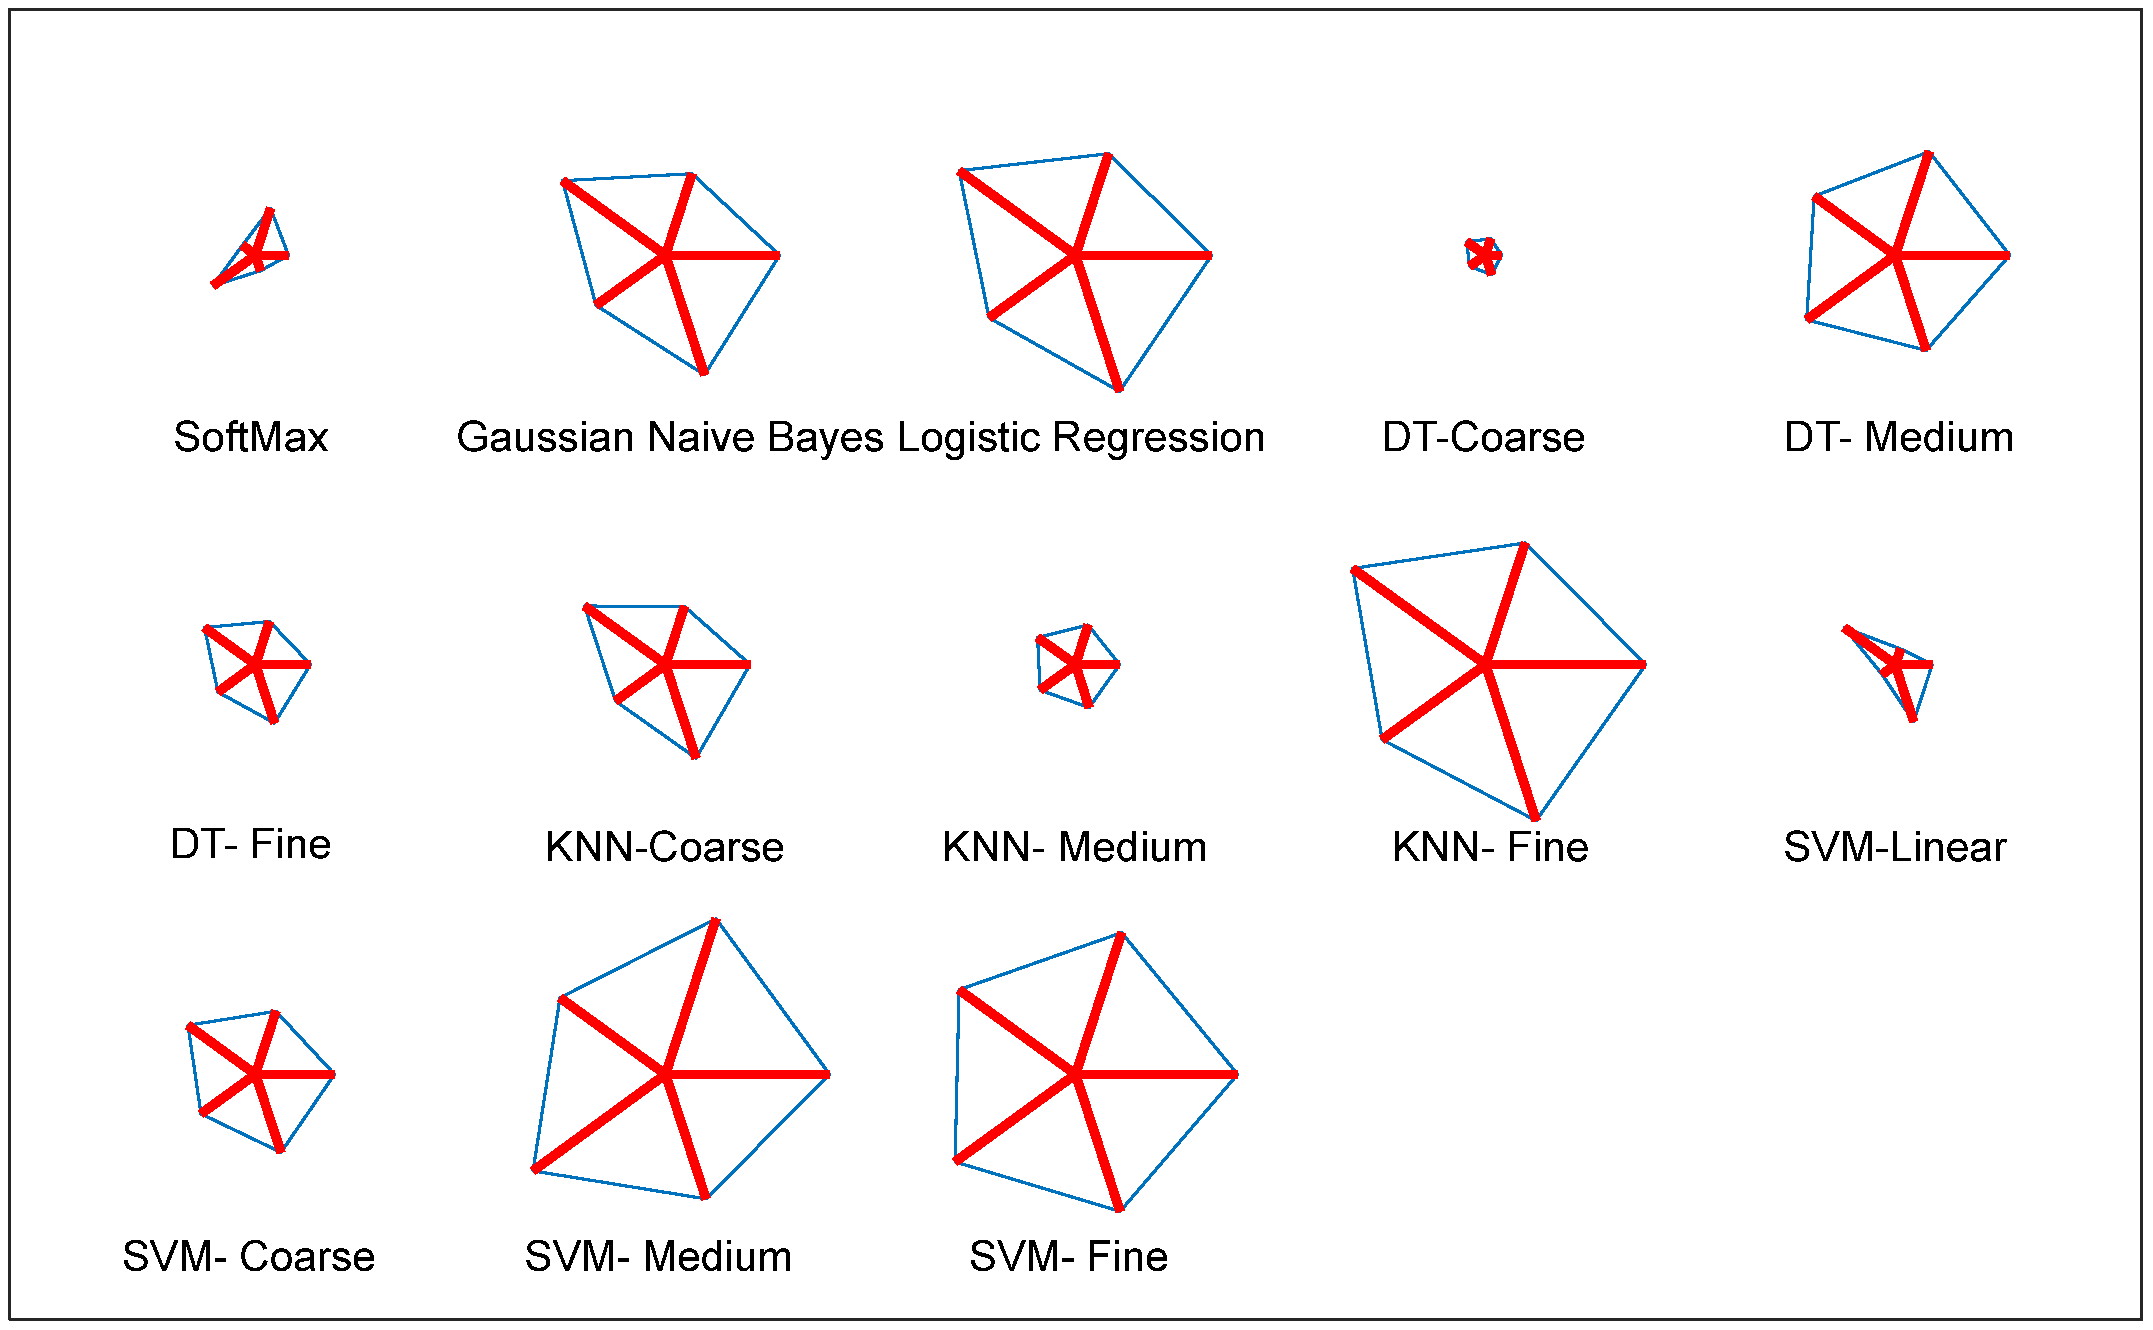

| Feature | Classifier | TP | FN | TN | FP | ACC% | PRE% | SEN% | SPE% | NPV% |

|---|---|---|---|---|---|---|---|---|---|---|

| DLF | SoftMax | 973 | 77 | 978 | 72 | 92.9048 | 93.1100 | 92.6667 | 93.1429 | 92.7014 |

| Gaussian Naive Bayes | 975 | 75 | 980 | 70 | 93.0952 | 93.3014 | 92.8571 | 93.3333 | 92.8910 | |

| Logistic Regression | 976 | 74 | 976 | 74 | 92.9524 | 92.9524 | 92.9524 | 92.9524 | 92.9524 | |

| DT-Coarse | 982 | 68 | 979 | 71 | 93.3810 | 93.2574 | 93.5238 | 93.2381 | 93.5053 | |

| DT-Medium | 981 | 69 | 983 | 67 | 93.5238 | 93.6069 | 93.4286 | 93.6190 | 93.4411 | |

| DT-Fine | 978 | 72 | 980 | 70 | 93.2381 | 93.3206 | 93.1429 | 93.3333 | 93.1559 | |

| KNN-Coarse | 981 | 69 | 986 | 64 | 93.6667 | 93.8756 | 93.4286 | 93.9048 | 93.4597 | |

| KNN-Medium | 974 | 76 | 979 | 71 | 93.0000 | 93.2057 | 92.7619 | 93.2381 | 92.7962 | |

| KNN-Fine | 977 | 73 | 982 | 68 | 93.2857 | 93.4928 | 93.0476 | 93.5238 | 93.0806 | |

| SVM-Linear | 982 | 68 | 977 | 73 | 93.2857 | 93.0806 | 93.5238 | 93.0476 | 93.4928 | |

| SVM-Coarse Gaussian | 980 | 70 | 983 | 67 | 93.4762 | 93.6008 | 93.3333 | 93.6190 | 93.3523 | |

| SVM-Medium Gaussian | 979 | 71 | 977 | 73 | 93.1429 | 93.0608 | 93.2381 | 93.0476 | 93.2252 | |

| SVM-Fine Gaussian | 982 | 68 | 981 | 69 | 93.4762 | 93.4348 | 93.5238 | 93.4286 | 93.5176 | |

| MLF | SoftMax | 841 | 209 | 864 | 186 | 81.1905 | 81.8890 | 80.0952 | 82.2857 | 80.5219 |

| Gaussian Naive Bayes | 853 | 197 | 848 | 202 | 81.0000 | 80.8531 | 81.2381 | 80.7619 | 81.1483 | |

| Logistic Regression | 856 | 194 | 851 | 199 | 81.2857 | 81.1374 | 81.5238 | 81.0476 | 81.4354 | |

| DT-Coarse | 849 | 201 | 862 | 188 | 81.4762 | 81.8708 | 80.8571 | 82.0952 | 81.0913 | |

| DT-Medium | 853 | 197 | 859 | 191 | 81.5238 | 81.7050 | 81.2381 | 81.8095 | 81.3447 | |

| DT-Fine | 863 | 187 | 861 | 189 | 82.0952 | 82.0342 | 82.1905 | 82.0000 | 82.1565 | |

| KNN-Coarse | 865 | 185 | 852 | 198 | 81.7619 | 81.3735 | 82.3810 | 81.1429 | 82.1601 | |

| KNN-Medium | 862 | 188 | 861 | 189 | 82.0476 | 82.0171 | 82.0952 | 82.0000 | 82.0782 | |

| KNN-Fine | 857 | 193 | 864 | 186 | 81.9524 | 82.1668 | 81.6190 | 82.2857 | 81.7408 | |

| SVM-Linear | 853 | 197 | 863 | 187 | 81.7143 | 82.0192 | 81.2381 | 82.1905 | 81.4151 | |

| SVM-Coarse Gaussian | 858 | 192 | 862 | 188 | 81.9048 | 82.0268 | 81.7143 | 82.0952 | 81.7837 | |

| SVM-Medium Gaussian | 861 | 189 | 864 | 186 | 82.1429 | 82.2350 | 82.0000 | 82.2857 | 82.0513 | |

| SVM-Fine Gaussian | 864 | 186 | 862 | 188 | 82.1905 | 82.1293 | 82.2857 | 82.0952 | 82.2519 |

| Classifier | TP | FN | TN | FP | ACC% | PRE% | SEN% | SPE% | NPV% |

|---|---|---|---|---|---|---|---|---|---|

| SoftMax | 993 | 57 | 1004 | 46 | 95.0952 | 95.5727 | 94.5714 | 95.6190 | 94.6277 |

| Gaussian Naive Bayes | 1026 | 24 | 1015 | 35 | 97.1905 | 96.7012 | 97.7143 | 96.6667 | 97.6901 |

| Logistic Regression | 1031 | 19 | 1022 | 28 | 97.7619 | 97.3560 | 98.1905 | 97.3333 | 98.1748 |

| DT-Coarse | 995 | 55 | 993 | 57 | 94.6667 | 94.5817 | 94.7619 | 94.5714 | 94.7519 |

| DT-Medium | 1018 | 32 | 1023 | 27 | 97.1905 | 97.4163 | 96.9524 | 97.4286 | 96.9668 |

| DT-Fine | 1007 | 43 | 1002 | 48 | 95.6667 | 95.4502 | 95.9048 | 95.4286 | 95.8852 |

| KNN-Coarse | 1018 | 32 | 1007 | 43 | 96.4286 | 95.9472 | 96.9524 | 95.9048 | 96.9201 |

| KNN-Medium | 1002 | 48 | 1001 | 49 | 95.3810 | 95.3378 | 95.4286 | 95.3333 | 95.4242 |

| KNN-Fine | 1037 | 13 | 1029 | 21 | 98.3810 | 98.0151 | 98.7619 | 98.0000 | 98.7524 |

| SVM-Linear | 1007 | 43 | 992 | 58 | 95.1905 | 94.5540 | 95.9048 | 94.4762 | 95.8454 |

| SVM-Coarse Gaussian | 1013 | 37 | 1009 | 41 | 96.2857 | 96.1101 | 96.4762 | 96.0952 | 96.4627 |

| SVM-Medium Gaussian | 1029 | 21 | 1042 | 8 | 98.6190 | 99.2285 | 98.0000 | 99.2381 | 98.0245 |

| SVM-Fine Gaussian | 1031 | 19 | 1036 | 14 | 98.4286 | 98.6603 | 98.1905 | 98.6667 | 98.1991 |